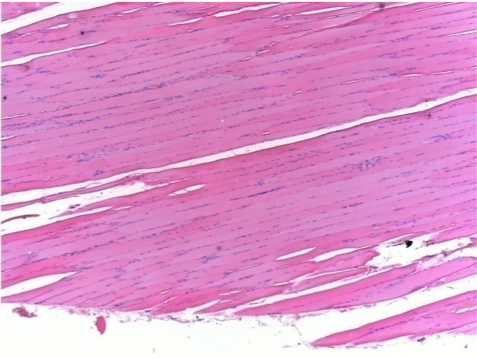

7 місяців (210 днів) після ін'єкції 0,1 мл Ендопіл в правий претибіальний м'яз.

Повна Restitutio ad integrum через 7 місяців

Л :Контроль 50x210 днів

П:50X-210 днів